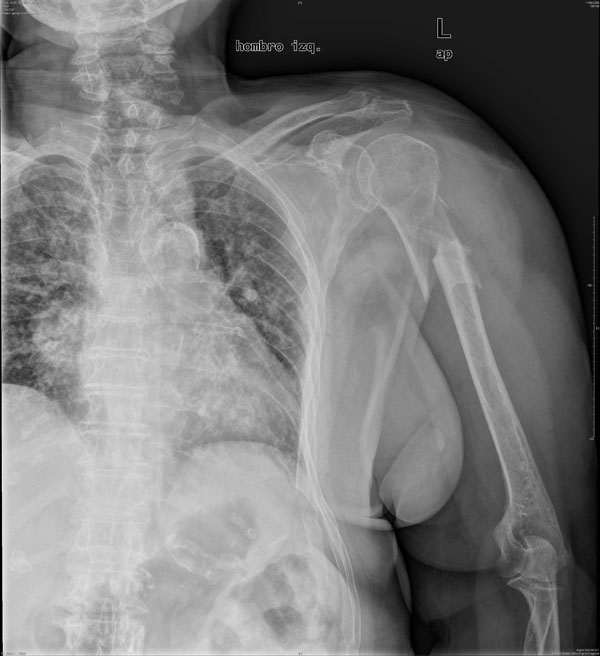

MO Fractura de omóplato y de costillas 2 a 8 derechas. Accidente de tráfico con moto en paciente centenaria. 1

MO Fractura de omóplato y de costillas 2 a 8 derechas. Accidente de tráfico con moto en paciente centenaria.2